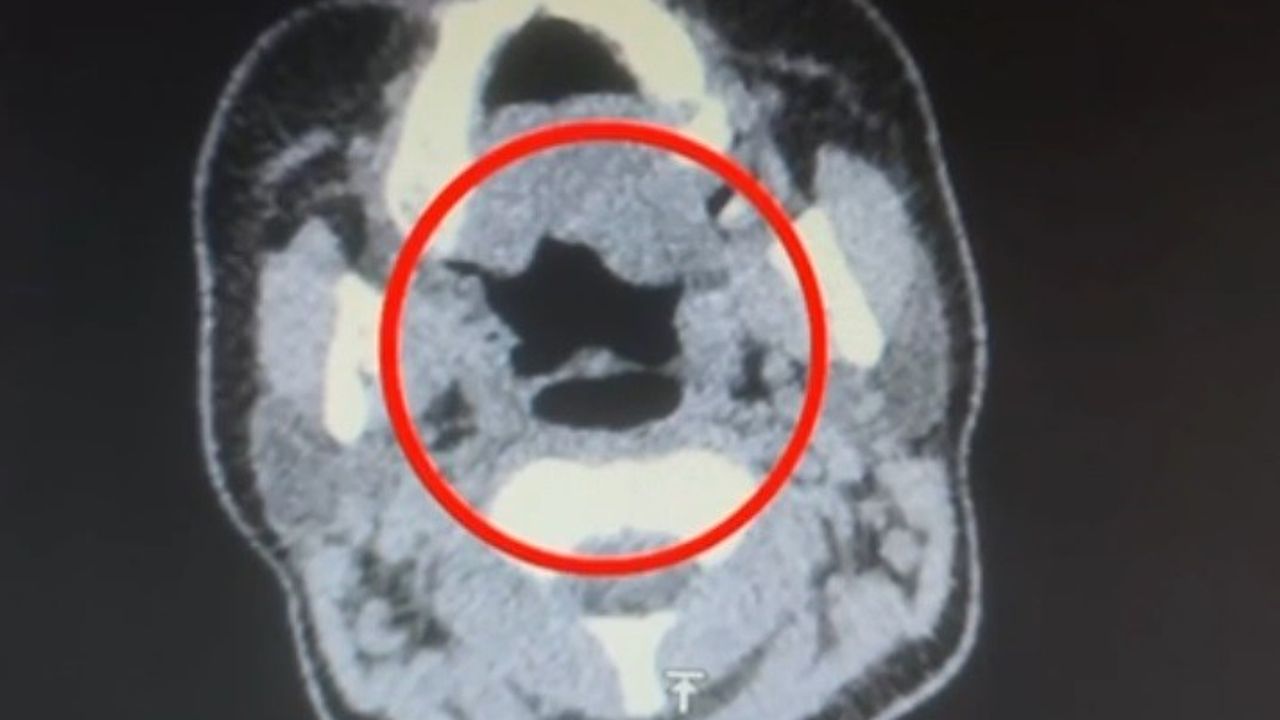

Şüpheli, hastaneye götürülerek iç beden muayenesine tabi tutuldu. Yapılan muayenede, şüphelinin midesinde 50 adet kapsül şeklinde toplamda 500 gram uyuşturucu madde bulunduğu tespit edildi.